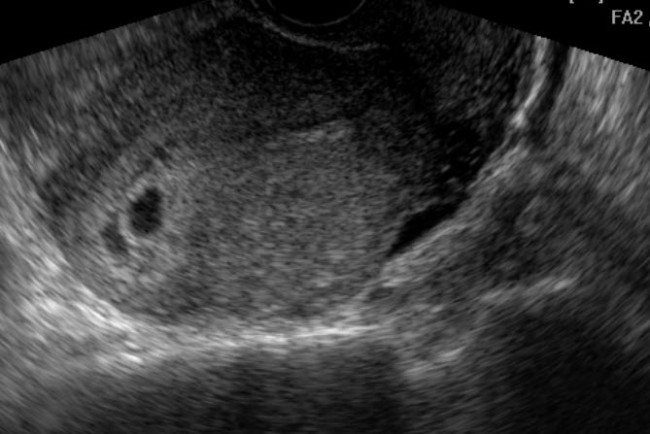

Хирургические процессы при эмболизации гемангиомы на фото

Раздел: Снимки-откровения